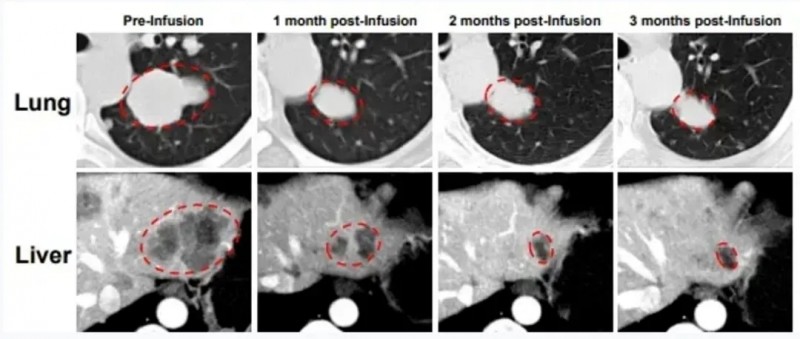

2024年美国临床肿瘤学会(ASCO)年会上,公布了我国首款无需清淋、也无需联合IL-2的TIL产品GC203,用于治疗复发性卵巢癌的Ⅰ期临床试验(NCT05468307)的振奋结果。

其中1例卵巢子宫内膜样癌患者,经包括PARP抑制剂、化疗在内的五线治疗后病情仍持续进展,接受GC203输注后达到部分缓解(PR),阳性率66%,目标病灶缩小(详见下图)。

▲图源“JUN CELL官网”,版权归原作者所有,如无意中侵犯了知识产权,请联系我们删除